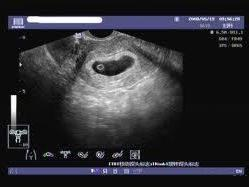

空孕囊是指孕婦在妊娠早期,胚胎發(fā)育異常或停止發(fā)育,導(dǎo)致孕囊內(nèi)沒(méi)有胚芽或胎心的情況,對(duì)于期待寶寶的家庭來(lái)說(shuō),空孕囊的出現(xiàn)無(wú)疑是一種打擊,了解空孕囊的征兆,早期識(shí)別并采取措施,對(duì)保障母嬰健康具有重要意義,本文將為您詳細(xì)解析空孕囊的十個(gè)征兆,以便您及時(shí)察覺(jué)并處理。

在孕早期后期或孕中期,通過(guò)B超應(yīng)能檢測(cè)到胎兒心跳,如無(wú)法檢測(cè)到胎兒心跳,可能是空孕囊的征兆。

通過(guò)B超檢查發(fā)現(xiàn)胚胎未按照正常時(shí)間發(fā)育,如未按時(shí)出現(xiàn)胚芽、胎心等,可能是空孕囊的表現(xiàn)。